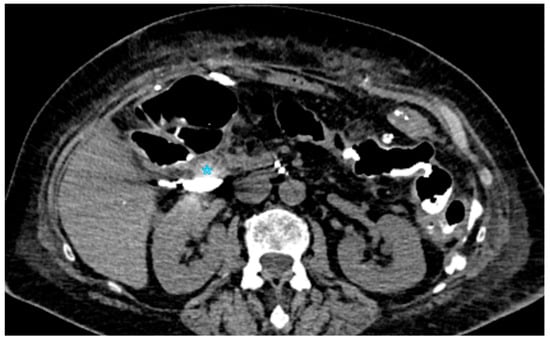

With an incidence ranging from 13% to 41%, postoperative pancreatic fistula (POPF) is the most common complication after pancreatic surgery and a major contributor to morbidity and mortality [141]. It is characterized by a detectable drain output that happens on or after the third postoperative day and an amylase concentration that is more than three times the typical serum level [20,22,41]. POPF can result in intra-abdominal abscesses and, in extreme situations, subsequent bleeding. It is caused by the leakage of pancreatic secretions at an anastomotic site or surgically removed surface. A tiny pancreatic duct, soft pancreatic texture, high-risk underlying disease, and substantial intraoperative blood loss are some of the variables that predispose individuals to POPF. Three grades of POPF are distinguished by the International Study Group of Pancreatic Fistula (ISGPF) [20]: Grade A, which is a biochemical leak without clinical symptoms; Grade B, which is defined by persistent drainage that lasts longer than three weeks and necessitates additional interventions like surgical or percutaneous drainage or presents complications like bleeding or infection; and Grade C, which requires reoperation and is linked to organ failure or death. For the purpose of directing management tactics and reducing serious difficulties, accurate classification is crucial.

Although the best time and indications for postoperative CT are still unknown, contrast-enhanced computed tomography (CECT) is the principal imaging modality used to diagnose POPF. The incidence of serious complications does not seem to be considerably impacted by routine early CT imaging during the first postoperative week. A structured methodology for early complication detection was recently presented by the PORSCH experiment [142]. It suggests CT scans based on clinical and laboratory indicators, including physical examination, changes in drain output, and blood test variations. According to a retrospective investigation, CECT on the seventh postoperative day provided an 83% specificity and 63% sensitivity for identifying POPF. Fluid collections close to the pancreaticojejunostomy site or resection margin, as well as obvious anastomotic disruption, are imaging characteristics diagnostic with Grade B or C POPF. The diagnosis is further supported by certain patients that exhibit aberrant connection with the main pancreatic duct.

Key CT features that differentiate severe (Grade C) POPF from milder cases (Grades A/B) were identified in a study by Lee et al. [143] that involved 235 postoperative patients. These features included acute necrotic collections, which indicated a more severe inflammatory process; pancreaticojejunostomy defects, which indicated incomplete or failed anastomosis; and pancreaticojejunostomy dehiscence, which is defined as a separation of >2 mm between the pancreatic duct and jejunal mucosa (Figure 3).

Secondary complications such as bleeding, pancreatitis, abscess development, and sepsis can also result with POPF; for proper clinical therapy, these conditions need to be carefully assessed on post-contrast CT [48,144]. The type of surgical treatment, the nature of the pancreatic lesion, the postoperative course, and individual patient factors are among the risk factors for postoperative pancreatic fistula that have been discovered. With an emphasis on body composition metrics and pancreatic parenchymal characteristics, recent research has examined preoperative CECT data to forecast POPF risk. Increased pancreatic gland thickness, pancreatic texture and borders, and a larger main pancreatic duct width are specific imaging markers linked to an increased risk of clinically severe POPF. Because pancreatic attenuation values may indicate underlying parenchymal fibrosis, they have also been linked to POPF risk. Furthermore, sarcopenia and visceral obesity have been associated with a higher risk of POPF, indicating that postoperative outcomes may be influenced by muscle and metabolic state [145,146]. By identifying these preoperative imaging indicators, surgical planning can be improved and risk can be stratified, which will ultimately lower the frequency and severity of postoperative pancreatic fistula.